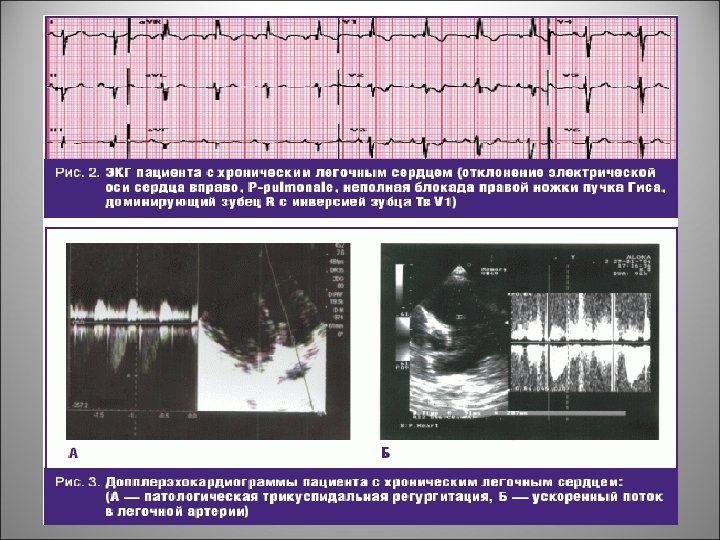

Дифференциальная диагностика обморочных (синкопальных) состояний • Определение давления в ЛА с помощью катетеризации, или косвенными методами (поликардиография, допплеркардиография трехстворчатого клапана, флебография или кинетокардиограммы). На ЭКГ признаки острого легочного сердца: повышение PII III av. F, появление правограммы, переходная зона к левым грудным отведениям, инфарктоподобные изменения ST и Т в правых грудных отведениях, быстрая динамика